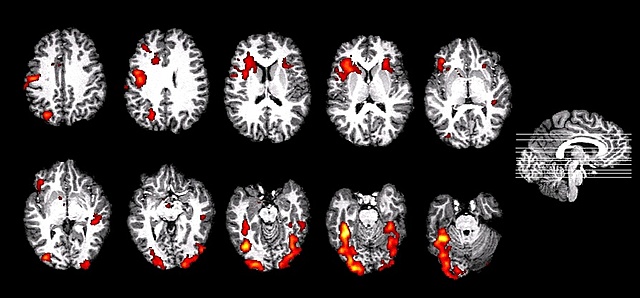

• Uso de la Resonancia Magnética Funcional para estudiar la habilidad lingüística - (2006).

Uso de la Resonancia Magnética Funcional para estudiar la habilidad lingüística - (2006).

Con el desarrollo de la tecnología de resonancia magnética funcional fue posible identificar qué áreas del cerebro se encuentran más activas durante ciertas actividades. En 2006, Byars, Holanda, Schithorst y Scaflarski (2006) realizaron una investigación utilizando esta tecnología para estudiar la lateralización del lenguaje en los cerebros de niños y adultos.